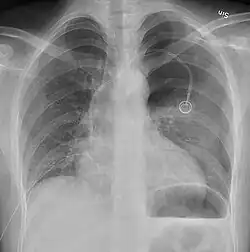

Chest tube

A chest tube placed on the right for a pneumothorax

A chest tube (or intercostal drain) is the most definitive initial treatment of a pneumothorax. These are typically inserted in an area under the axilla (armpit) called the "safe triangle", where damage to internal organs can be avoided; this is delineated by a horizontal line at the level of the nipple and two muscles of the chest wall (latissimus dorsi and pectoralis major). Local anesthetic is applied. Two types of tubes may be used. In spontaneous pneumothorax, small-bore (smaller than 14 F, 4.7 mm diameter) tubes may be inserted by the Seldinger technique, and larger tubes do not have an advantage.[18][52] In traumatic pneumothorax, larger tubes (28 F, 9.3 mm) are used.[46] When chest tubes are placed due to either blunt or penetrating trauma, antibiotics decrease the risks of infectious complications.[53]

Chest tubes are required in PSPs that have not responded to needle aspiration, in large SSPs (>50%), and in cases of tension pneumothorax. They are connected to a one-way valve system that allows air to escape, but not to re-enter, the chest. This may include a bottle with water that functions like a water seal, or a Heimlich valve. They are not normally connected to a negative pressure circuit, as this would result in rapid re-expansion of the lung and a risk of pulmonary edema ("re-expansion pulmonary edema"). The tube is left in place until no air is seen to escape from it for a period of time, and X-rays confirm re-expansion of the lung.[18][22][38]